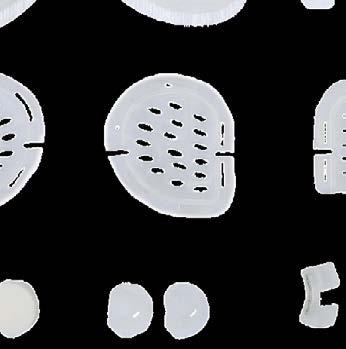

Niet iedereen wordt geboren met mooi gevormde oren. In Nederland wordt 33% van de baby’s geboren met, in meer of mindere mate, een afwijking in de vorm van de oren. Afstaande oren, ofwel flaporen, komen het meest voor. De afgelopen 5 jaar heeft plastisch chirurg Michelle Feijen onderzoek gedaan naar oorcorrecties bij baby’s, zonder dat daar een operatie aan te pas kwam. In de studie behandelde Drs. Feijen 74 baby’s met zo’n 6 verschillende oorafwijkingen, zoals een gevouwen oortje, misvormde oorschelp en flaporen.

Behandeling noodzakelijk binnen 6 weken na de geboorte

De behandeling bestaat uit het aanbrengen van het EarWell systeem. Het kapje zorgt ervoor dat de oren van je baby op de juiste manier gevormd worden en corrigeert binnen 4 tot 6 weken de afwijking. De behandeling heeft een succesgarantie van 95%, is pijnloos en er zitten geen risico’s aan voor het kindje. Belangrijk is wel dat de behandeling tijdig start, het liefst in de 2e of 3e week na de geboorte. Mogelijk moeten de oortjes van je baby nog enkele weken worden afgeplakt na het verwijderen van het EarWell systeem. Harderwijkweg 3a, 2803 PW Gouda +31 85 48 84 470 www.esserclinics.nl

De behandeling bestaat uit het aanbrengen van het EarWell systeem. Het kapje zorgt ervoor dat de oren van je baby op de juiste manier gevormd worden en corrigeert binnen 4 tot 6 weken de afwijking. De behandeling heeft een succesgarantie van 95%, is pijnloos en er zitten geen risico’s aan voor het kindje. Belangrijk is wel dat de behandeling tijdig start, het liefst in de 2e of 3e week na de geboorte. Mogelijk moeten de oortjes van je baby nog enkele weken worden afgeplakt na het verwijderen van het EarWell systeem. Revolutionaire

De resultaten zijn baanbrekend, omdat deze behandeling een operatie op latere leeftijd voorkomt. Met de oorkapjes van EarWell kunnen de meest voorkomende oorafwijkingen effectief worden gecorrigeerd, zonder operatie. Esser Clinics voert deze innovatieve behandeling uit, waarbij de behandeling binnen de eerste weken na de geboorte begint.